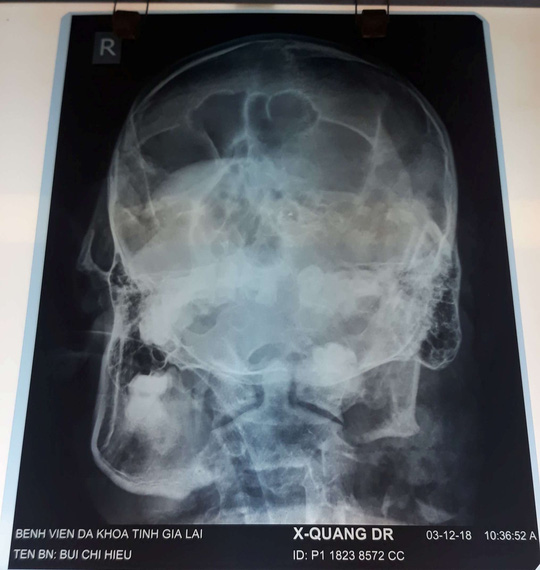

Theo Bệnh viện Đa khoa tỉnh Gia Lai, đơn vị tiếp nhận bệnh nhân Hiếu vào lúc 10 giờ 25 phút ngày 3-12, từ bệnh viện tuyến dưới chuyển lên. Theo hồ sơ ban đầu, bệnh nhân tự bắn vào đầu, trình trạng đang hôn mê, suy hô hấp, mất ý thức, cảm giác, phản xạ, dập nát vùng mặt và cằm, huyết áp chỉ còn 50/90.